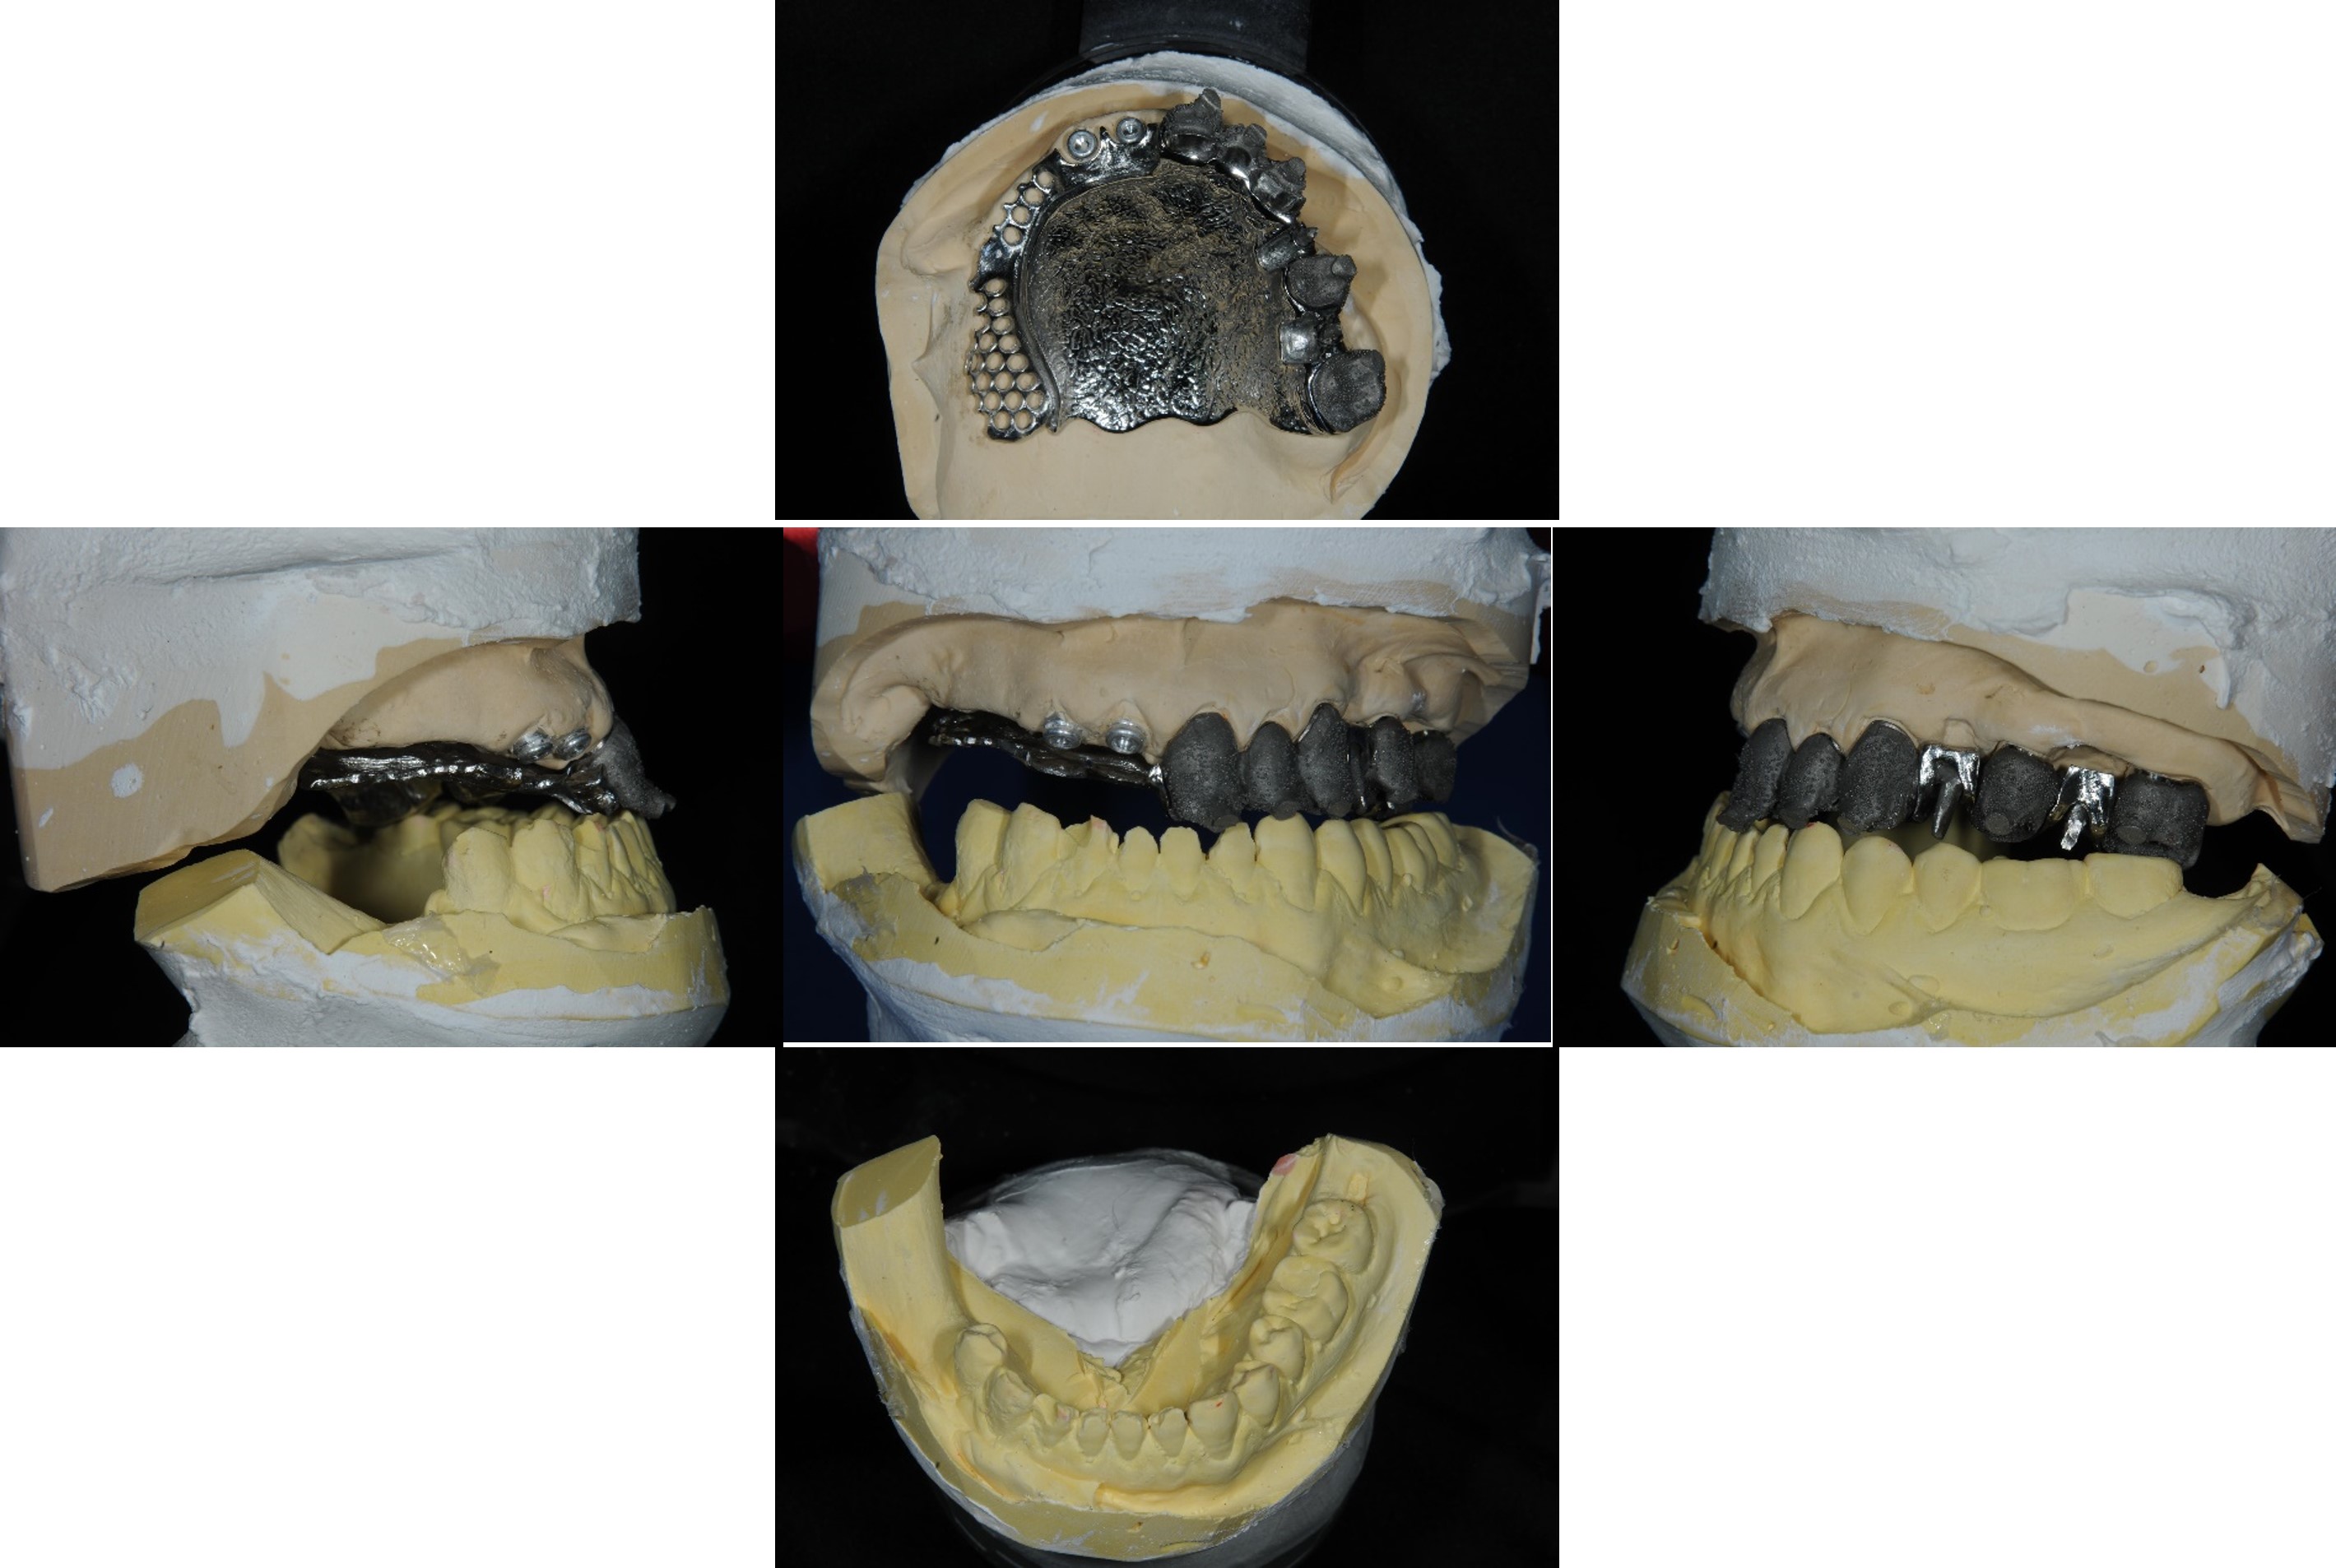

模型咬合分析

蠟型模擬最終可能成果